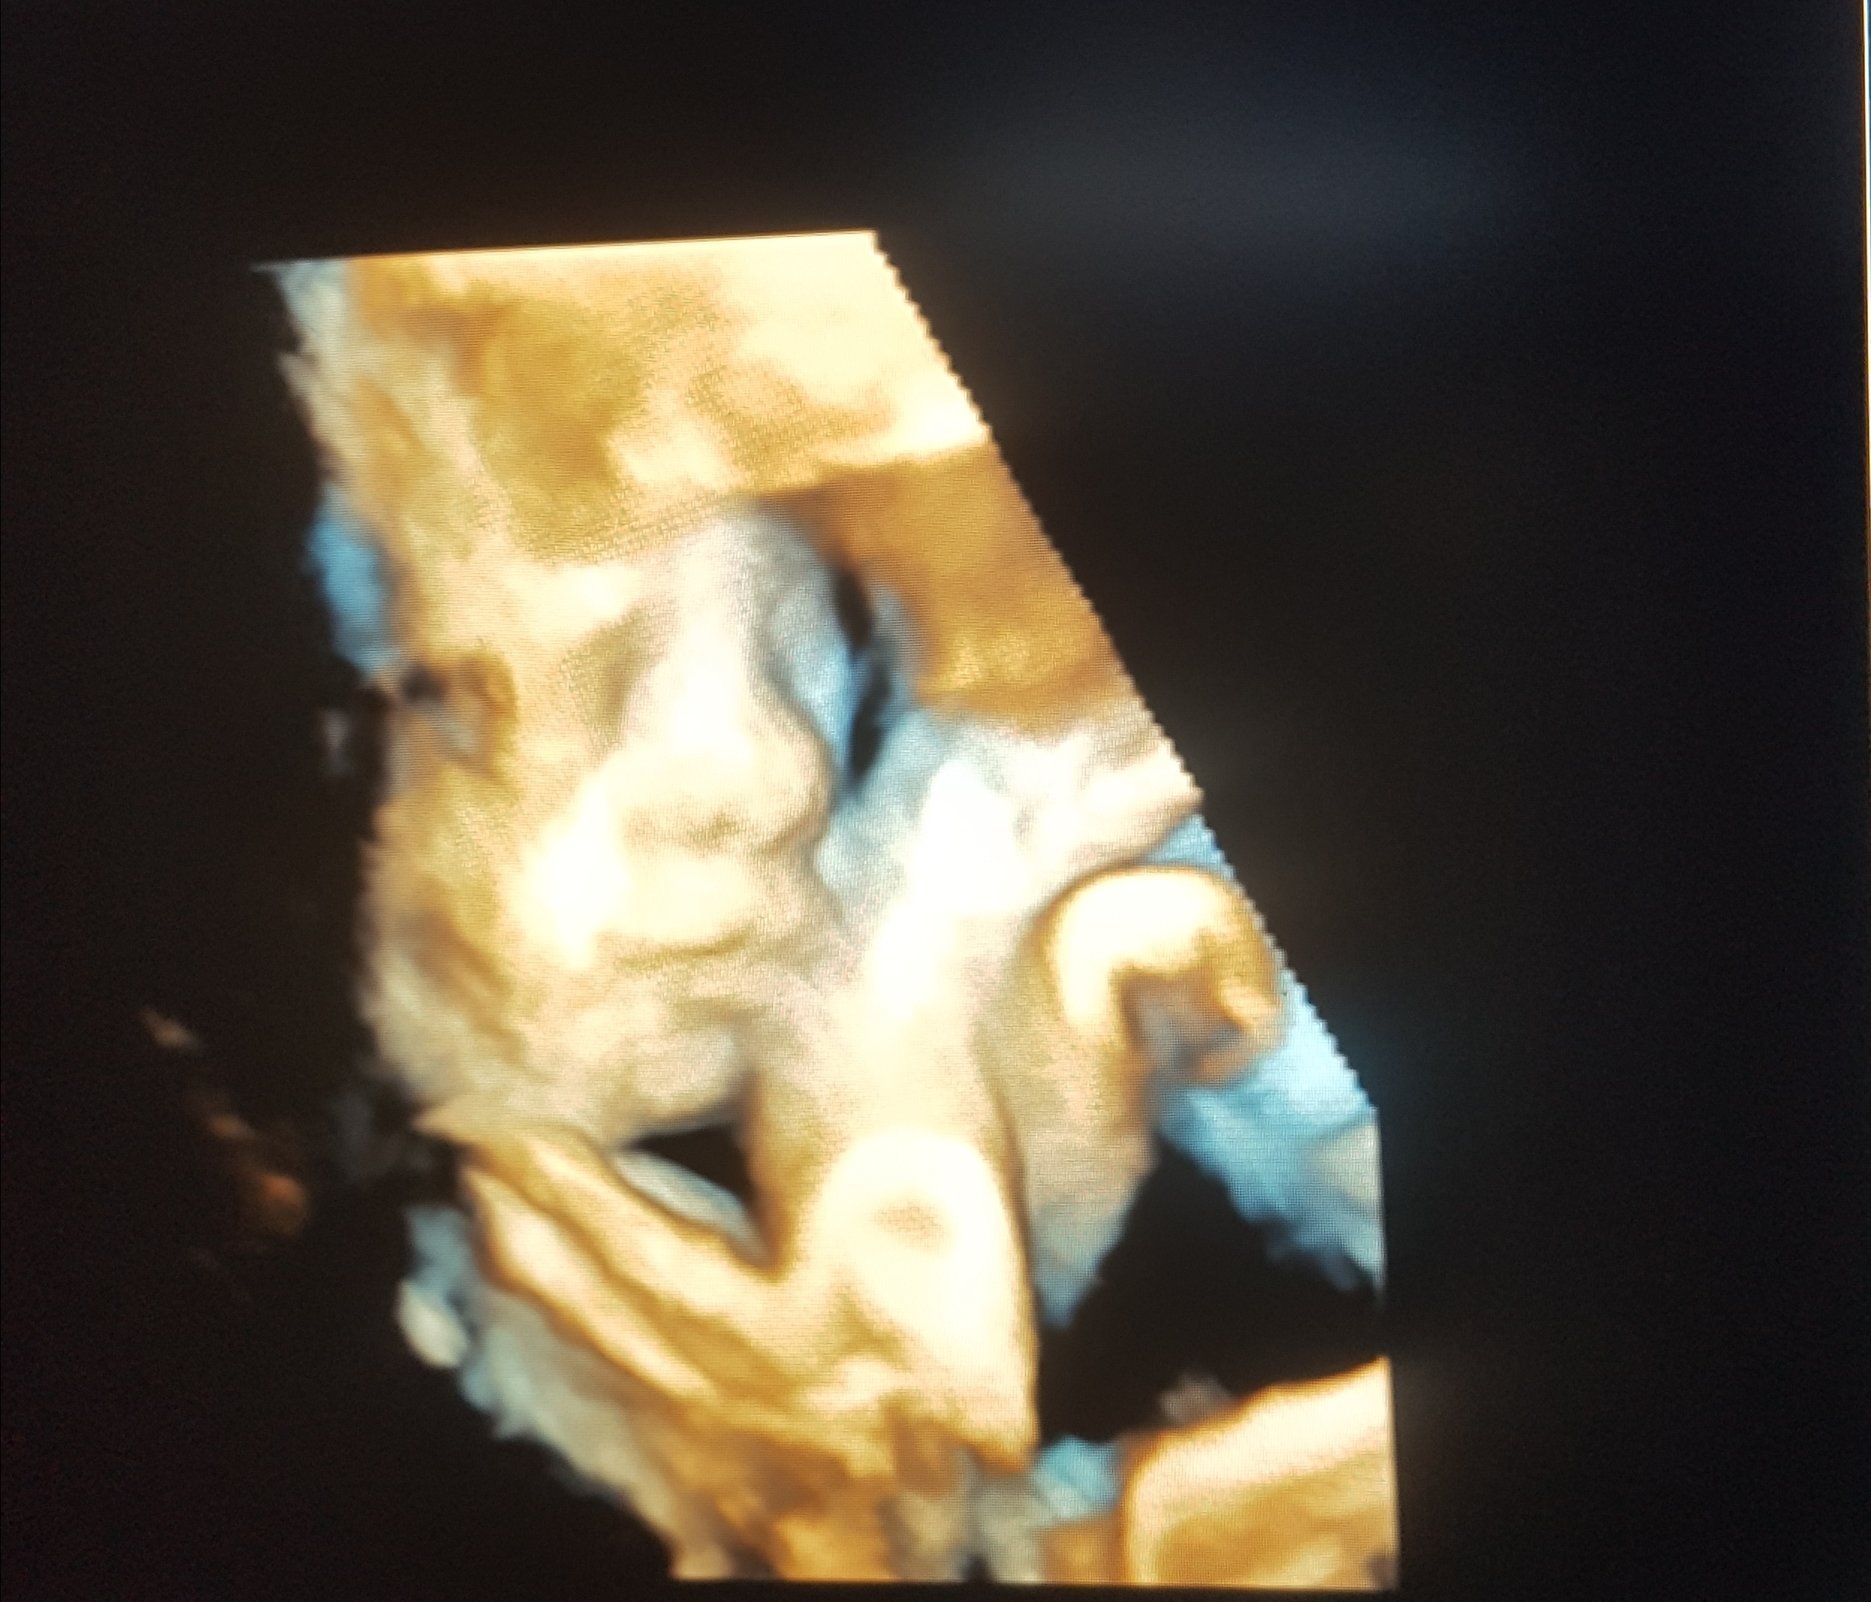

This was my last ultrasound from 16w1d, today I am 18 weeks but she’s already has her mama’s attitude lol. She decided to show us her feet first then decided to give us her glamour shot